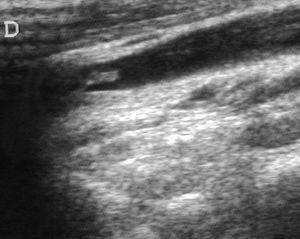

Ante la sospecha de síndrome de Lemierre, se realizó ecografía doppler cervical que evidenció una trombosis de la VYI derecha (fig. 3), confirmándose el diagnóstico y añadiéndose al tratamiento heparina de bajo peso molecular.

Figura 3. Ecografía cervical: sección longitudinal laterocervical derecha mostrando vena yugular interna derecha ocupada por formación ecogénica con extremo libre flotante.